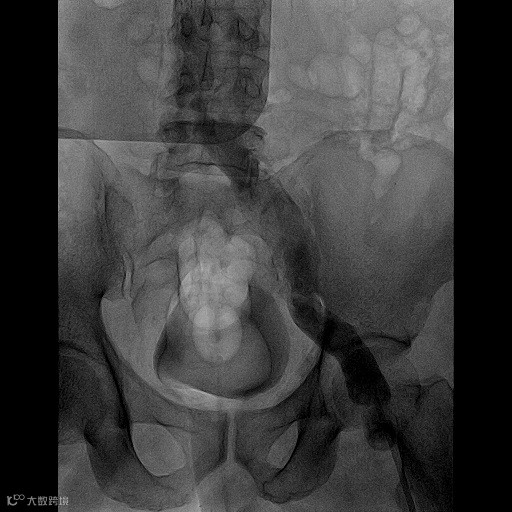

由沈阳市第一人民医院介入科陈建军主任团队运用中天天航™Pro血栓抽吸导管治疗一例急性左下肢深静脉血栓形成且伴有右下肢血流淤滞病变,成功清除血栓并快速恢复肢体灌注,欢迎大家阅读、分享、交流!

手术过程